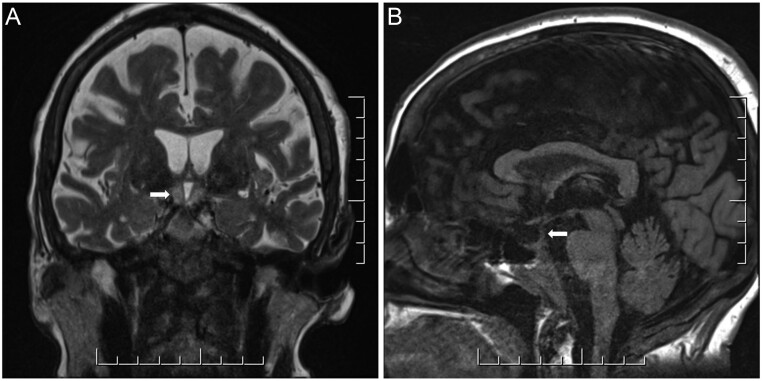

Her complete blood count (CBC) showed leukocytosis (22.5 × 109/L) with numerous blasts (7.3 × 109/L), normochromic anemia (69 g/L), and moderate thrombocytopenia (74 × 109/L). Cytogenetics on bone marrow biopsy revealed translocation of chromosomes t(12;14)(p12;q13) and pathogenic variants in NPM1, DNMT3A, and PTPN11. An MRI of the brain for the assessment of neurologic involvement revealed symmetric high-T2 signal within the hypothalamus extending into the mamillary bodies bilaterally without obvious enhancement, a partially empty sella, and loss of the pituitary bright spot (Fig. 1). A lumbar puncture showed no blasts.

Figure 1.

MRI of the brain showing symmetric high T2 signal within the hypothalamus extending into the mamillary bodies bilaterally (A), a partially empty sella and loss of the pituitary bright spot (B). Image quality was degraded by motion artifact.

Interestingly, the majority (61.4%) of patients with AML-associated CDI have no abnormalities in brain imaging (2). In this case, MRI revealed a symmetrical high-T2 signal in the hypothalamus, a partially empty sella, and loss of the pituitary bright spot. While the loss of the pituitary bright spot by itself is a non-specific finding, a partially empty sella and symmetric enhancement at the hypothalamus is rare (1, 2). We found only one other study which showed symmetrically enhanced lesions in the hypothalamus in a patient with myelodysplastic syndrome and CDI (7). Although uncommon, previous autopsy studies have shown evidence of peri-pituitary leukemic infiltration in patients both with and without clinical CDI (8, 9). However, the absence of supporting imaging findings in the majority of patients with AML makes the pathogenesis of CDI unclear, and several alternate mechanisms related to cytogenetic abnormalities have been proposed as well (2, 3, 4).